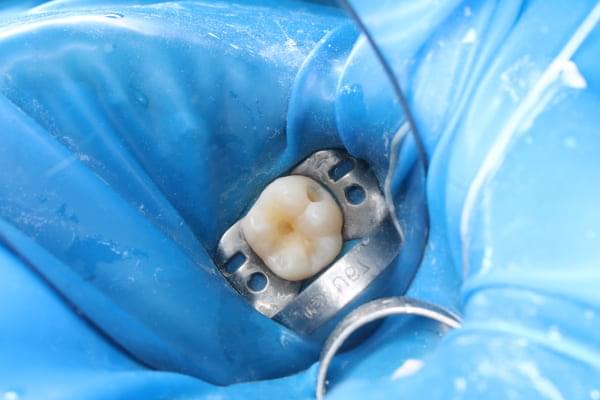

Поява перших постійних зубів, а це шості зуби, відбуваються, коли дитина ще не може, як слід провести їх гігієну та попіклуватись про їх здоров’я. Тому, на жаль вони і вражаються карієсом досить швидко. Пацієнт ще маленький – 6 років, а лікування потребує дорослого: зі знеболенням та ізоляцією. Саме таке і було проведене в даному випадку: зуб очищений від інфікованих тканин, відновлений фотополімерним матеріалом і готовий довго служити юному господарю.